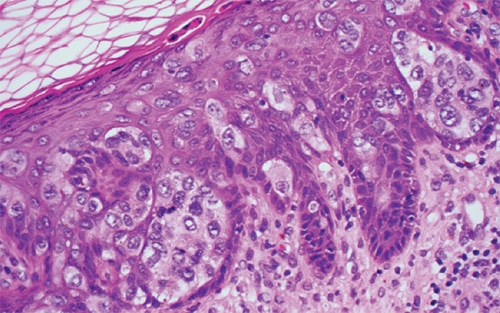

Paget disease of nipple

Context

- Paget disease is the presence of breast carcinoma within the nipple epidermis.

- The majority of lesions are associated with underlying DCIS or invasive carcinoma.

Clinical findings

- The cutaneous changes resemble eczema: crusted erythematous lesions with scale.

Prototypical morphology

- Large cells with abundant pale cytoplasm are present within the epidermis, arranged singly (“buckshot”) or in small groups (Figure 5-13).

- The cells have atypical nuclear features and intracytoplasmic mucin.

- A lichenoid dermal infiltrate may be seen.

Special studies

- Paget cells are consistently positive for CK7 and mucin stains.

- They are variably positive for carcinoembryonic antigen (CEA), epithelial membrane antigen (EMA), GCDFP, and GATA3.

- HER2 is overexpressed in most cases, and ER/PR are usually negative.

- Paget cells are negative for high-molecular-weight keratins, p63, and melanocytic markers.

- The immunophenotype of Paget cells may be indistinguishable from benign Toker cells; they are distinguished based on cytologic atypia.

Treatment and prognosis

- Prognosis and treatment depend on presence of underlying invasive carcinoma.

- Pure Paget disease, without underlying malignant breast lesion, has excellent overall survival, with lymph node metastases being rare.